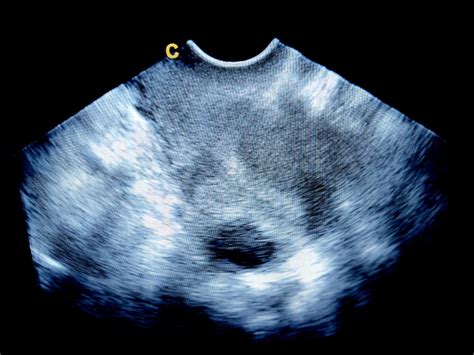

- Ciste na jajčnikih: Včasih lahko obstoječe ciste na jajčnikih postanejo bolj opazne ali povzročajo nelagodje med nosečnostjo. Rumeno telesce, ki nastane po ovulaciji in je ključno za zgodnjo nosečnost, se nahaja v jajčniku in lahko povzroča občutek bolečine ali tiščanja. Običajno se v 10. tednu nosečnosti to rumeno telesce še vedno aktivno vzdržuje, kar lahko prispeva k občutkom v jajčnikih.

V 10. tednu nosečnosti je tveganje za izvenmaternično nosečnost že nekoliko manjše kot v zelo zgodnjih tednih, vendar je še vedno prisotno, še posebej pri ženskah z dejavniki tveganja (npr. prebolele okužbe medeničnih organov, predhodne operacije jajcevodov ali maternice, zanositve s pomočjo asistirane reprodukcije). Če se bolečine v jajčnikih ali spodnjem delu trebuha močno poslabšajo, so konstantne, ostre ali jih spremlja krvavitev, je obisk zdravnika nujen.